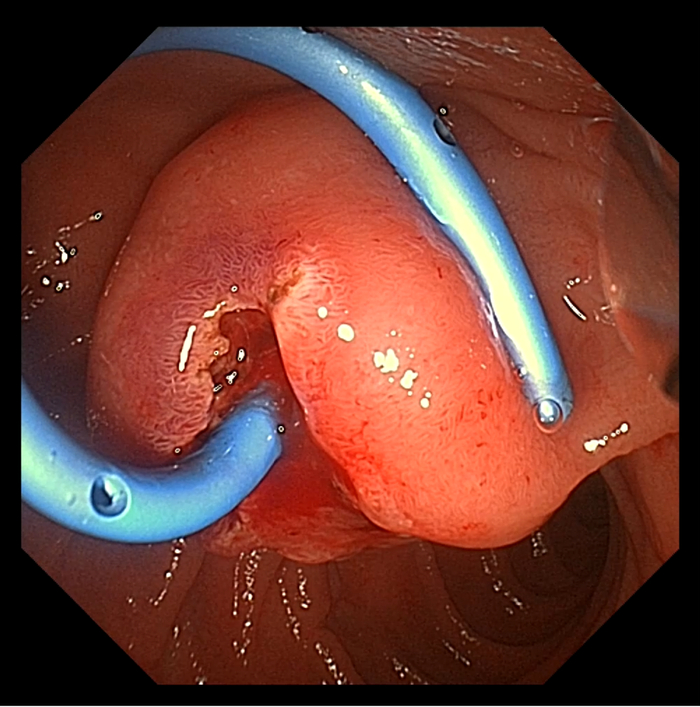

患者男,65岁。于十二指肠内侧找见主乳头,乳头呈鼻型,开口呈绒毛样。胆管狭窄导致反复超选导丝无法进入,后使用一次性粘膜切开刀,沿胆管方向行预切开,再次插管导丝进入胆管,注入少量造影剂,胆管显彰。

患者于三月后更换胆管支架,十二指肠镜应用操作如图所示: